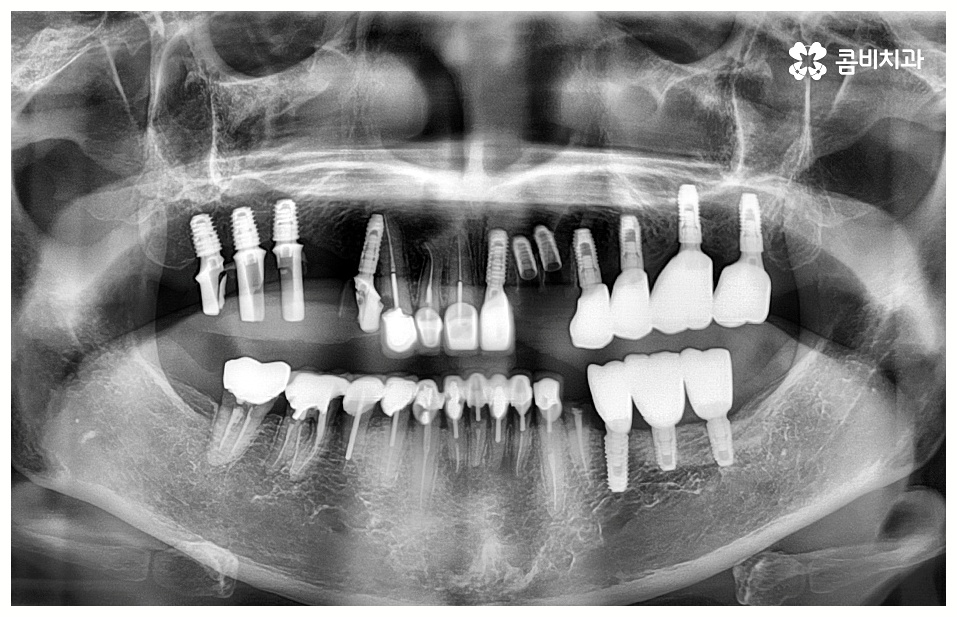

임플란트 시술을 받을 때 많은 분들이 궁금해 하시는 것 중 하나가 임플란트 치료기간 그리고 수명에 대한 것일 텐데요, 먼저 기간은 대략적으로 3~6개월 정도 걸린다고 알려져 있으나 환자마다 잇몸뼈 상황이나 전체적인 건강 상태 및 회복력이 다르기 때문에 환자분들에 따라 다르게 적용되고 있는 부분이고 그에 따라 임플란트 치료기간 또한 달라질 수 있습니다.

예를 들어서 잇몸뼈가 튼튼하다면 발치 후 즉시 임플란트 식립 시술을 할 수 있어서 임플란트 치료기간 이 줄어들고 보다 간편한 수복이 가능할 것이나 주변 잇몸에 염증이 남아있어서 먼저 치료를 해야 하거나 바탕이 되는 잇몸뼈의 밀도, 높이 등이 부족하여 보충이 필요한 경우에는 뼈이식 과정을 우선 진행해야 하기 때문에 임플란트 치료기간 이 길어질 수 있어요.

임플란트 치료는 자신의 자연 치아를 대신해 오랫동안 쓸 수 있도록 장기적인 안정성을 추구하는 것이 중요하기 때문에 최초의 진단과 치료 계획을 꼼꼼하게 세우는 것이 필수라고 할 수 있어요.

또한 풍부한 임상 경험과 노하우를 가진 숙련된 의료진, 다각적이고 체계적인 분석을 할 수 있는 3D CT 와 같은 정밀 분석 장비를 갖추고 보다 안정성이 검증된 정품 재료의 사용 여부 등을 잘 체크해야 할 거예요.